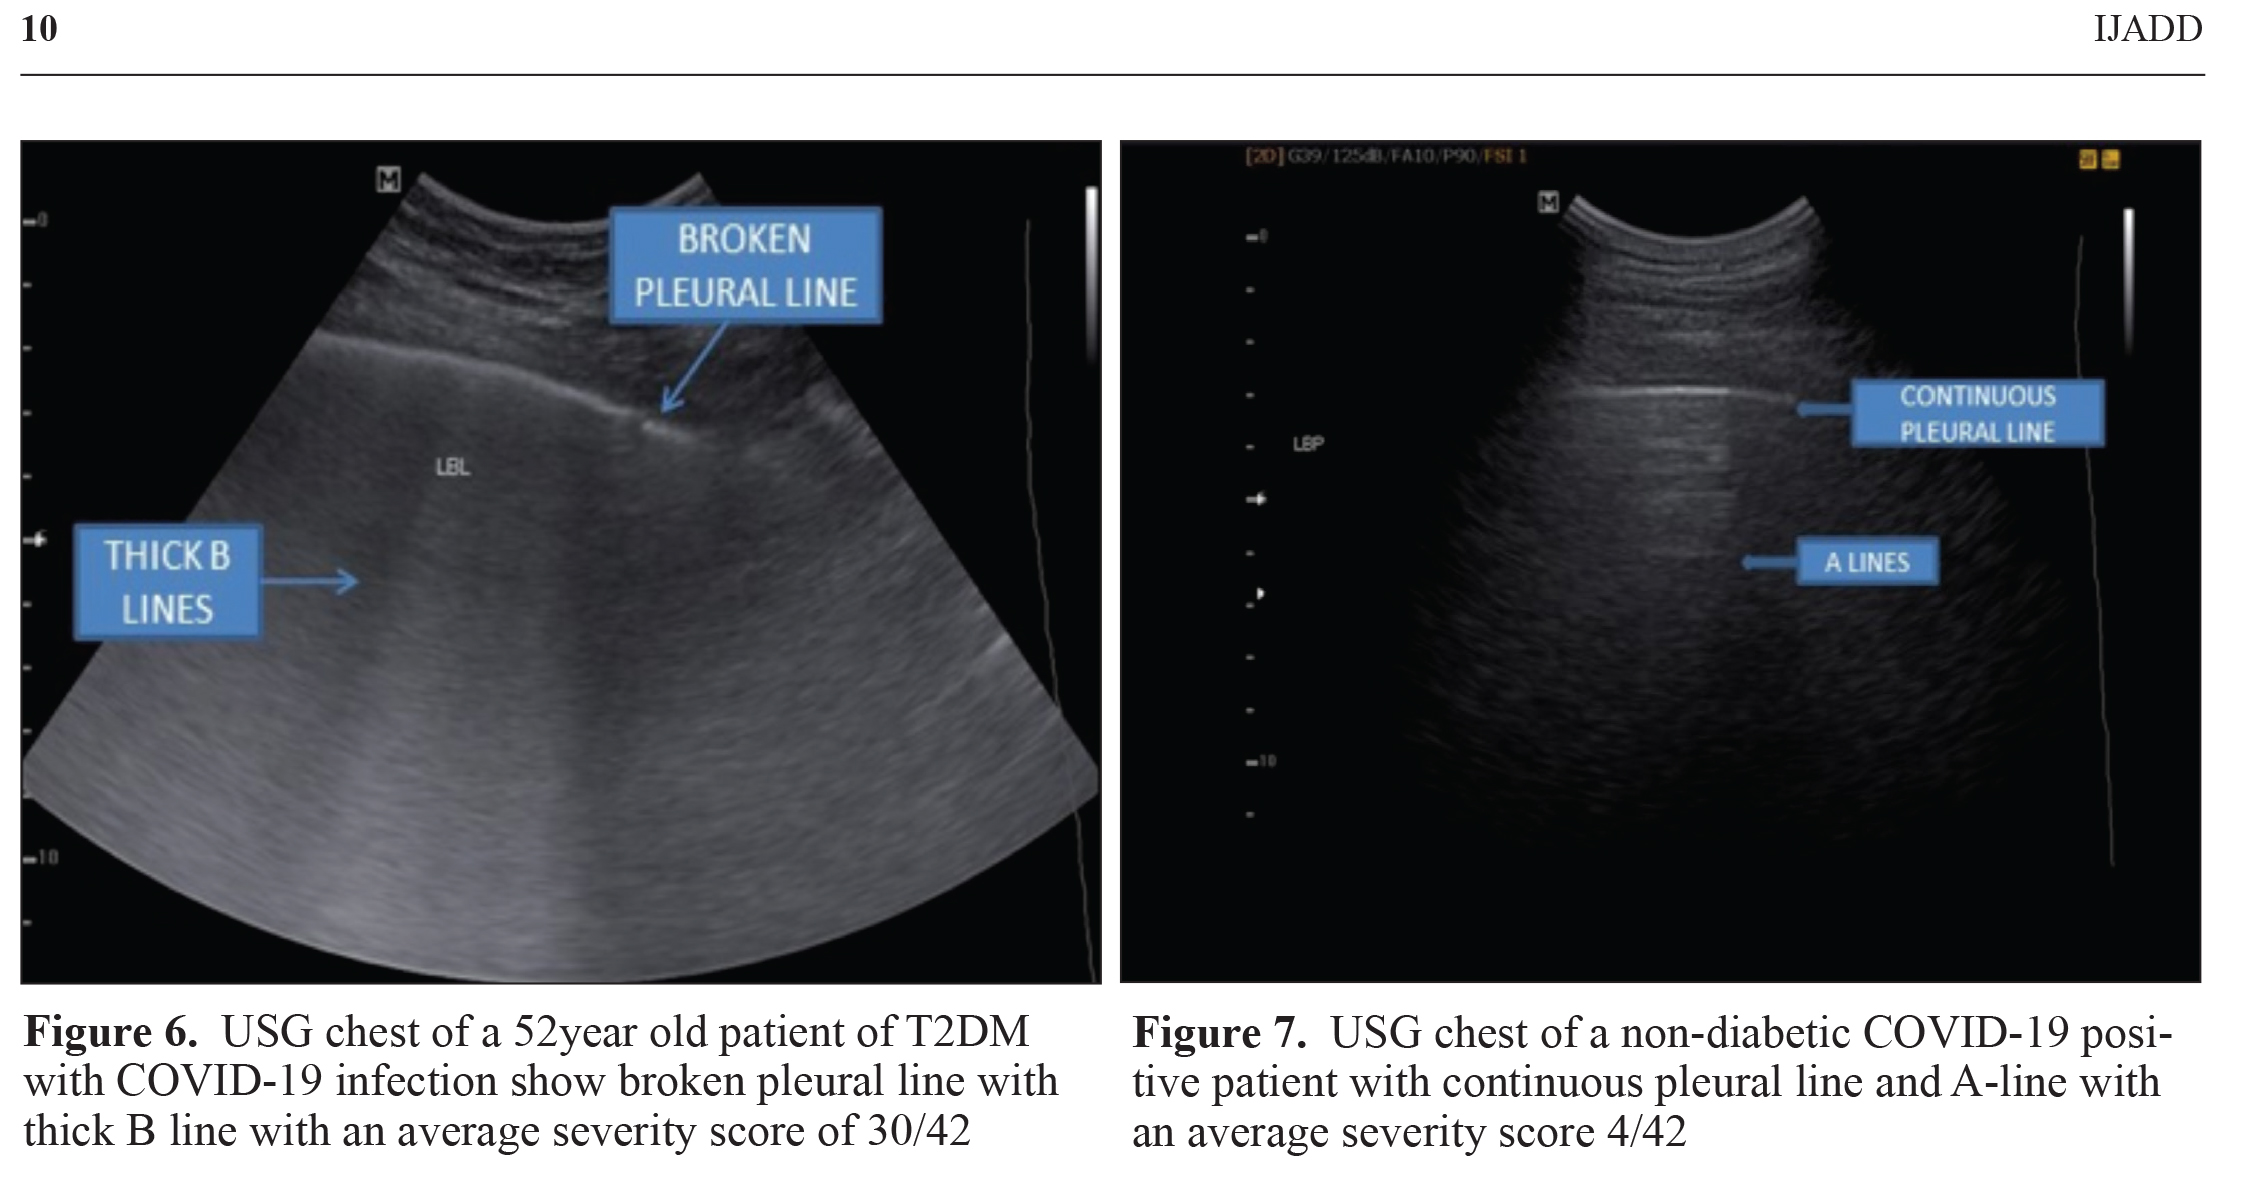

Digital chest radiograph (CXR) of all patients, USG chest of 200 patients (15.87%) and HRCT chest of 424 patients (33.65%)was available for analysis. CXR depicted a classic for COVID images in 208 patients (16.51%) with an average visual score of0.63±0.81 out of 4. USG severity score was 14.88±9.18 out of 14 and average CT severity score was observed to be 5.81±5.44out of 25 with CT severity score >10/25 in 80 patients (18.87%) (Figure 4 and 5). Radiological findings observed amongdiabetes group and non-diabetes group without comorbidities were as follow: The CXR average visual score was 0.74 and 0.58(p=0.0035) while classic for COVID images was observed in 28.57% and 13.06% patients (p<0.001) in Group 3 and Group4 respectively. USG chest severity score was significantly higher in diabetes group (17.86) as compared to the non-diabetesgroup (13.48) (p=0.0041) (Figure 6 and 7). CT severity score was 7.24 in the diabetes group and 5.32 in the non-diabetesgroup (p=0.0020) with a CT severity score >10/25 in 29.41% and 15.53% patients in the respective groups (p=0.0018).

Radiological imaging of chest provides an important clue regarding lung involvement in COVID-19 that is a prognosticindicator of disease severity. Digital chest X-ray imaging suggested a higher proportion of sample population exhibiting lung involvement in diabetics as compared to that observed in non-diabetics. A similar picture was portrayed by CT severityscore that was high in diabetic patients as compared to the findings of non-diabetics. However, USG chest severity score wassignificantly increased in the isolated diabetic group as compared to the non-diabetes group without other comorbidities. Theaforementioned findings suggest a severe form of pneumonia in diabetic patients as compared to the non-diabetic patients.Moreover, COVID-19 manifestation and its severity are adversely affected by the associated comorbid disease. In the presentstudy, clinical presentation and laboratory parameters indicated a significant difference among isolated diabetes and the non-diabetes group without comorbidities, compared to groups, with comorbidities.